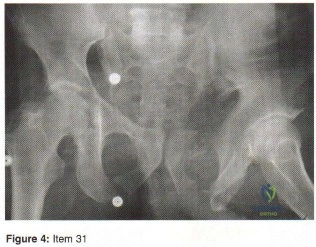

- Sacral fracture lateral to the foramina

- Sacral fracture medial to the foramina

- Sacroiliac fracture-dislocation

- Sacroiliac dislocation

- Iliac wing fracture